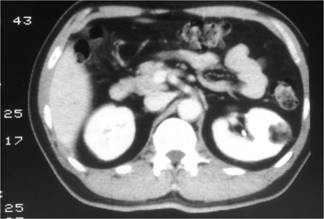

這題的解題核心在於辨識腎臟腫瘤影像中的「脂肪成分」。圖片中左腎腫瘤內有明顯的低密度區域,這是判斷的關鍵。